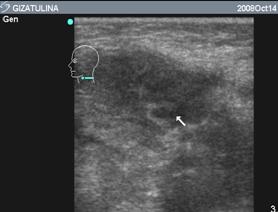

Эхограмма этой же больной через три дня после вскрытия и дренирования гнойника (рис. 6.Б), обращает уменьшение размеров участка гнойного расплавления, отсутствие гнойного затека. Что говорит об эффективности лечения. На следующем рисунке (рис. 7), представлена эхограмма этой же пациентки, выполненная на 11 сутки, с практически восстановленной структурой лимфоузла.

Таким образом, благодаря эхографическому исследованию можно выявить стадию гнойного расплавления, точно локализовать процесс, проследить динамику и предупредить возможные осложнения. Также метод позволяет проследить результат лечения после хирургического вмешательства.

Рис. 7. Эхограмма лимфоузла на 11 сутки после хирургического лечения